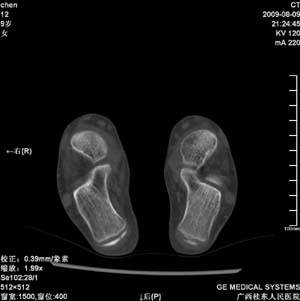

标题: PED2867:右侧内踝肿胀,骨质改变,请各位老师会诊 [打印本页]

标题: PED2867:右侧内踝肿胀,骨质改变,请各位老师会诊

九岁小朋友,近期左侧内踝疼痛,局部肿胀,平时无特殊,近期经常溜干冰

对不起,是右侧内踝肿胀

双侧踝关节骨质及关节结构均未见明显异常。考虑玩多了累的,休息休息看看吧!

骨质及关节结构未见异常。